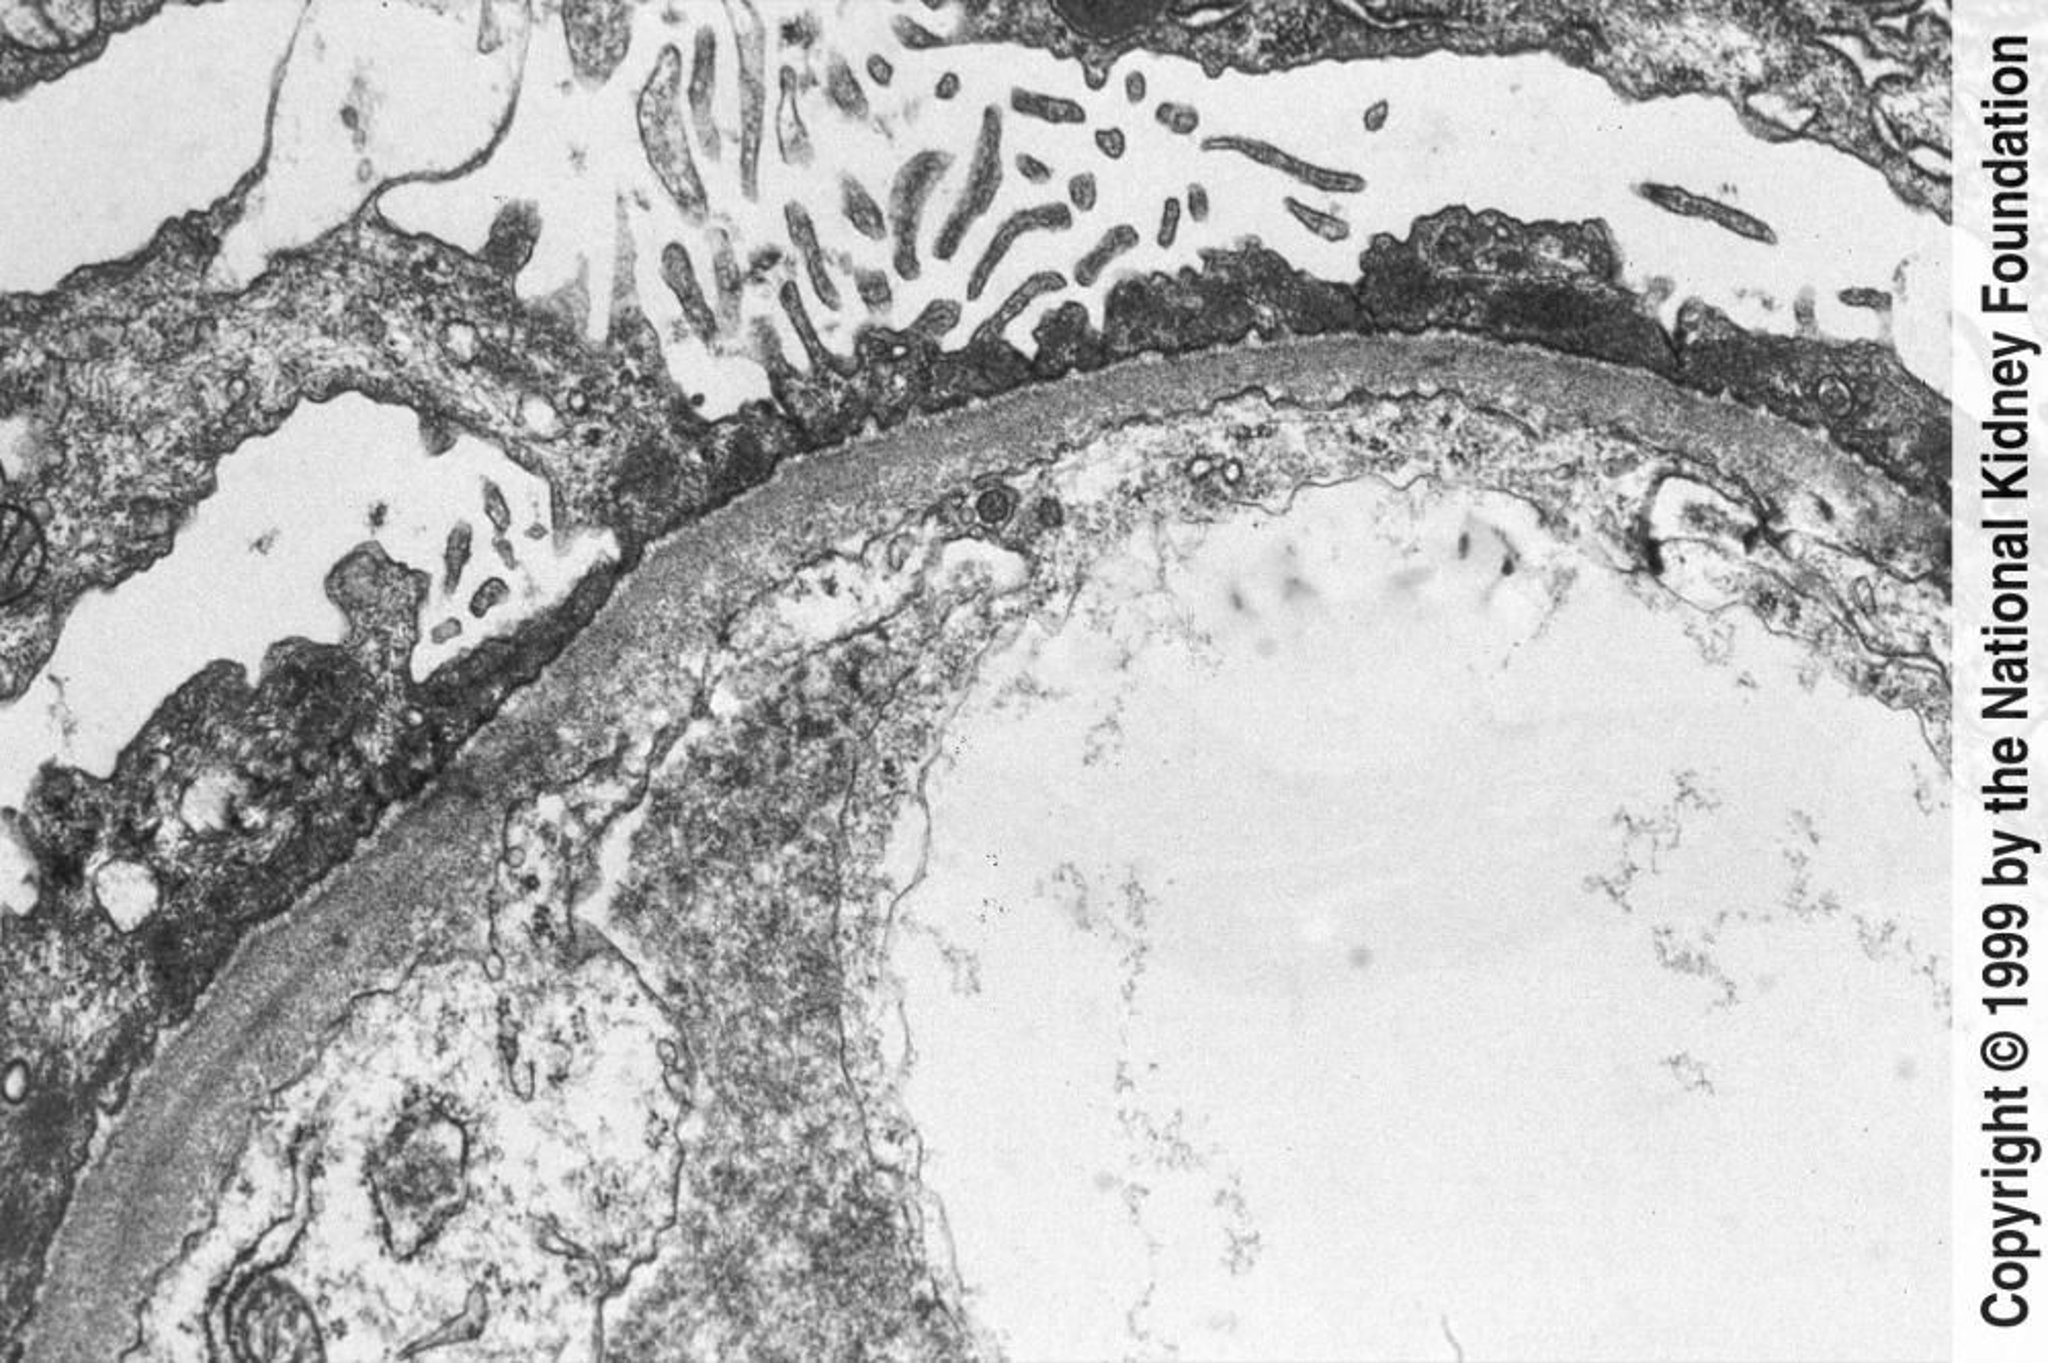

Enfermedad de cambios mínimos

En la microscopia electrónica de transmisión puede observarse el borramiento difuso de los pedicelos (×800).

Image provided by Agnes Fogo, MD, and the American Journal of Kidney Diseases' Atlas of Renal Pathology (véase www.ajkd.org).